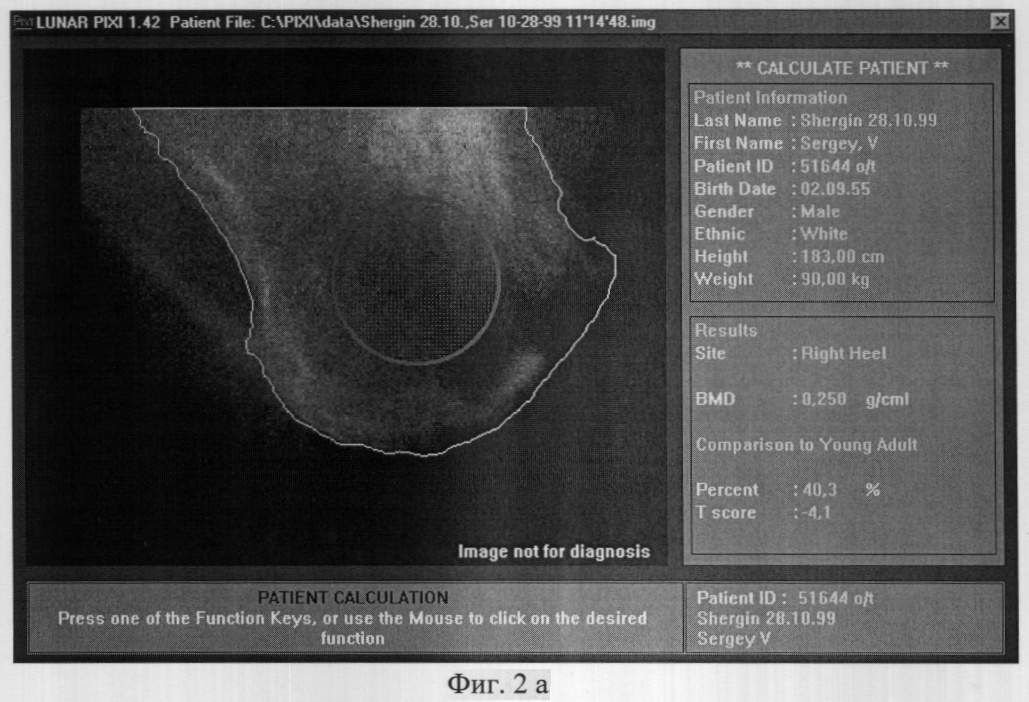

До операции 13.04.2000 года больному проведено исследование минеральной плотности костной ткани (МПКТ) левой пяточной кости, на денситометре фирмы LUNAR (США) и 12.04.2000 года исследование показателя реографического индекса (РИ) левой голени, на реографе “РИСТА-131-РЕО” (г.Таганрог). Выявили следующие данные:

– МПКТ левой пяточной кости – 0,450 г/см2 (см. фиг.1а);

– РИ левой голени – 0.027 Ом (см. фиг.1 b).

Прогноз сращения перелома благоприятный – менее 6-ти месяцев, т.к. МПКТ выше 0.300 г/см2, а РИ выше 0.02 Ом.